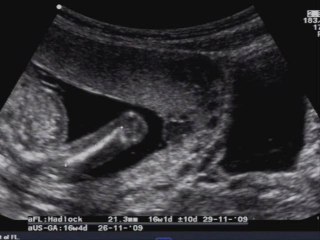

Ecografia Ostetrica 20 settimane